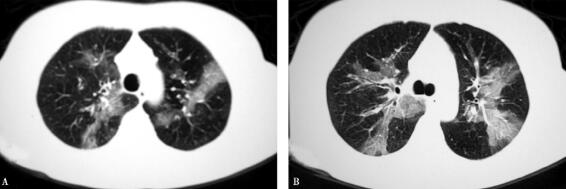

1.胸部CT(2011年12月7日):双肺上叶散在磨玻璃、斑片样浸润影(图1)。

图1

予甲泼尼龙每日40mg及其他平喘药物治疗10天后(2011年12月19日)复查胸部CT,症状好转,肺部干鸣音消失,胸部CT示双肺斑片状浸润影明显吸收(图3)。复查血常规:白细胞计数8.2×109/L,中性粒细胞百分比75.5%,嗜酸粒细胞百分比0.7%。糖皮质激素治疗后病情明显好转。继续口服糖皮质激素,逐渐减量共计服用1年,症状控制。目前停用糖皮质激素半年余,未复发。

图3